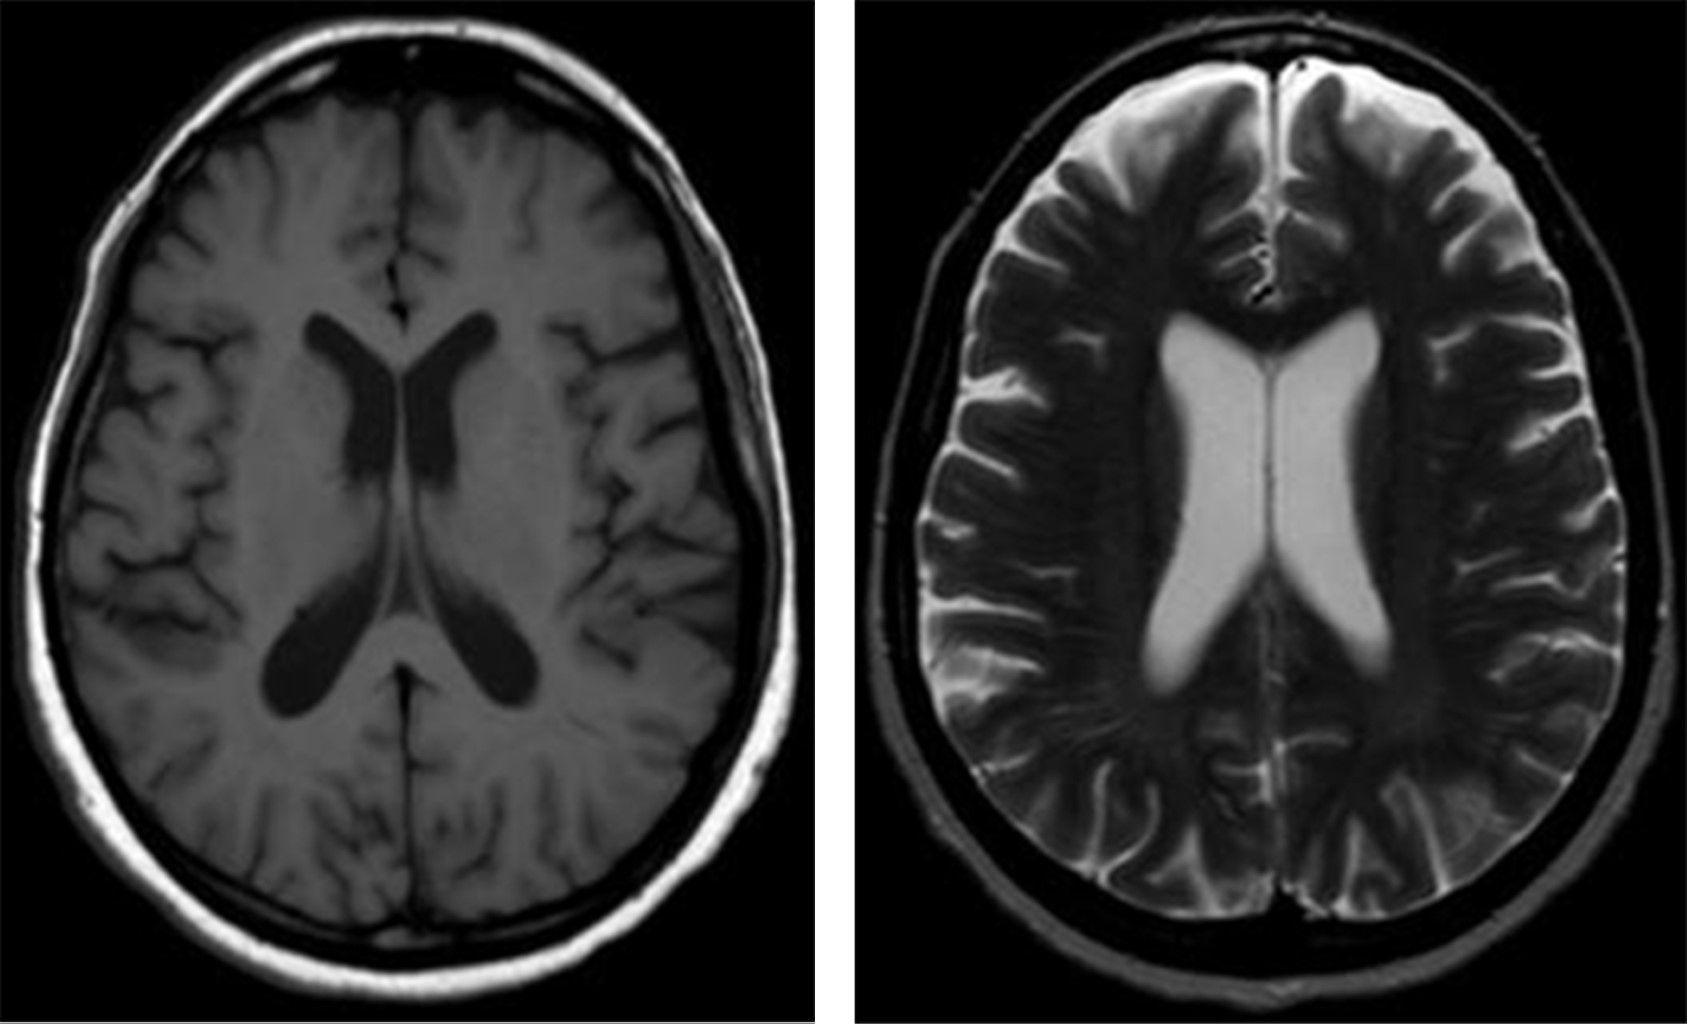

b) Evolución intrahospitalaria. Durante su estancia intrahospitalaria en psiquiatría continúa con la misma sintomatología, con desorientación en autopsíquica y alopsíquica (en función de tiempo y espacio), irritabilidad, agresividad, capacidad de concentración disminuida, funciones mentales no valorables, lenguaje incoherente, incongruente, ideas delirantes de daño y referencia, alucinaciones visuales, juicio desviado, pobre control de impulsos e intolerancia a la frustración. A la exploración neurológica se evidencia temblor intencional, disartria, ataxia cerebelosa, disdiadococinesia, apraxia ideomotora y del vestido, leve disminución de la fuerza en extremidades inferiores con alteraciones para la marcha. Exploración de pares craneales, reflejos osteotendinosos y función sensorial se encuentran sin alteraciones. El día 28 de septiembre del 2019 se reportaron niveles séricos de litio con 0.15 mEq/l. Se toma resonancia magnética con reporte del 15 de octubre, en el que se informa pérdida de volumen hacia la porción rostral de los lóbulos frontales y temporales de manera bilateral, sugestiva de atrofia cortico subcortical en esta región anatómica (Figuras 1 y 2). Posteriormente, el 18 de octubre se realiza electroencefalograma con resultado anormal, con signos de moderada alteración funcional cortico subcortical difusa con discreto predominio anterior bilateral.

Figura 2